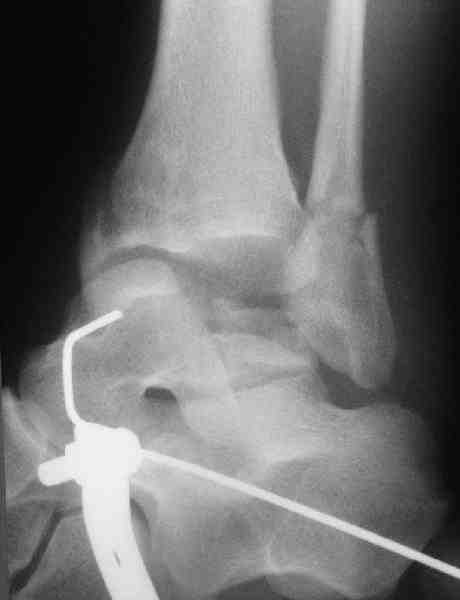

Interesting case

The ankle joint looks ruined. I wonder howcome is it as ruined after 2 days. I would open the joint( Some people would artroscope it) and judge the osteosynthes vs ankle fusion according to the ankle joint condition. The subtalar does not look injured, but if you feel there is a clinical

problem- CT it. Above all- when I see such an X-Ray I call the resident who ordered it and tell him that I would expect him first thing to reduce it on arrival since the soft tissue suffer and I hope that currently the p-nt is reduced to some extent at least.

Sorry- I revised it and the talus is fractured- take him to the theater at once and reduse it with Int Fix

The soft tissue will be a problem- Ex Fix will be better thn plaster

а основании двух видов ренгенограмм невозможно радикально решить о необходимости открытой репозиции или первичного артродеза.

Для оценки состояния нужны дополнительные исследования, например Canale или Broden ренгенограммы и Компьютерная томография.

При переломах тарана всегда имеется риск AVN, а классификация Hawkins поможет разобраться с предполагаемыми осложнениями.

Если в первом типе, когда перелом шейки без смещения, тогда AVN менее 10%, при втором типе когда имеется смещение и вывих тарана в субталарном сочленении меньше 40%, а при типе III когда смещение в голеностопном и субталарном суставах - около 90% и в типе IV, когда происходит полный вывих, риск AVN достигает 100%.

Идеально фиксацию провести в первые часы, но не всегда возможно из-за отека, поэтому временный наружный фиксатор на дистракцию поможет уменьшению отека и даст время для адекватного обследования.